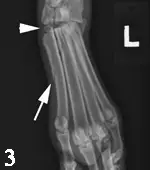

Diagnosis (Figure 3): These findings indicate a fracture of the 2nd metatarsal bone (arrow) and, more importantly, subluxation of the tarso-metatarsal articulation (arrowhead). In human medicine, this is called a Lisfranc injury and is most commonly identified in athletes.

Outcome: This subluxation needs to be stabilized surgically. Intramedullary pins were placed spanning the 2nd through 4th metatarsal bones through the tarso-metarsal joints. The patient had an excellent outcome and no lameness was observed 9 weeks postoperatively.